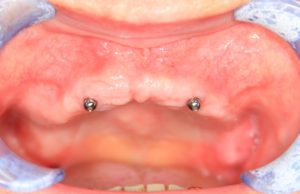

Можно установить два имплантата с замками в определенные участки зубного ряда и фиксировать съемный протез к этим замкам: